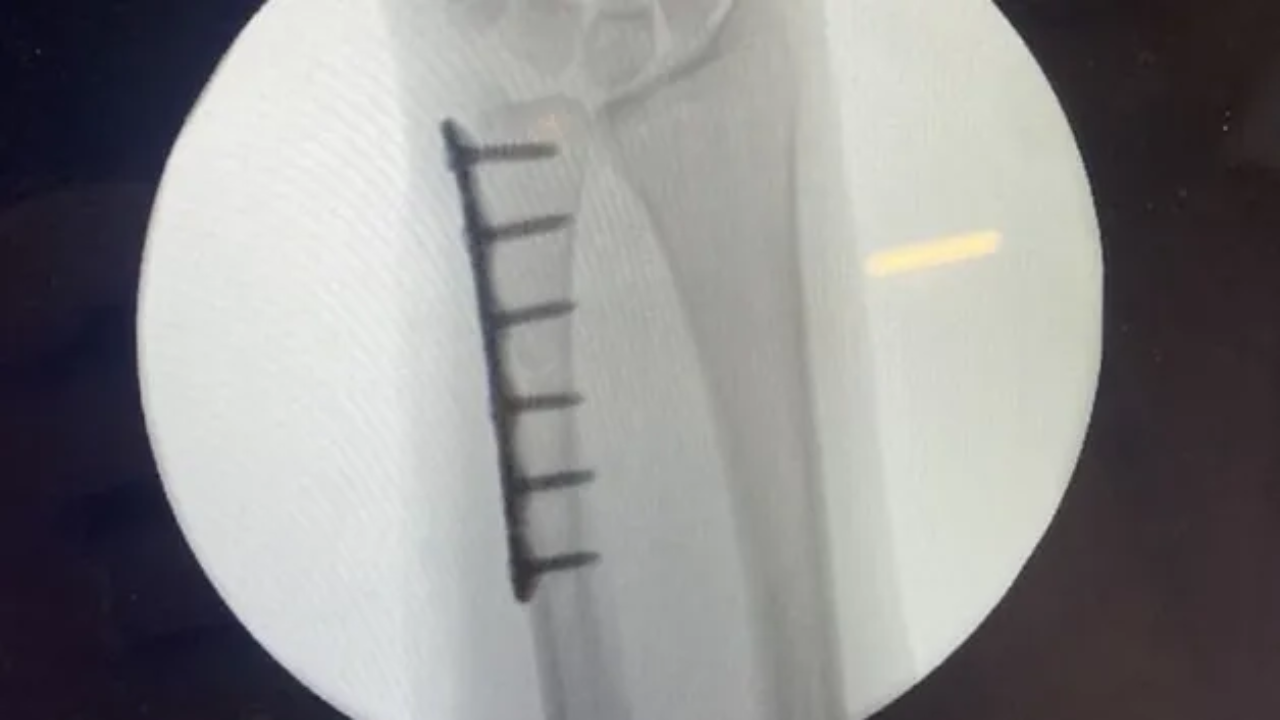

Injuries are part of the game, but they can be tough mentally ang physically. A few weeks ago, I broke my ulna while playing softball, and it's been a challenging journey. Surgery, rehab, and missing key competitions have been difficult to face.